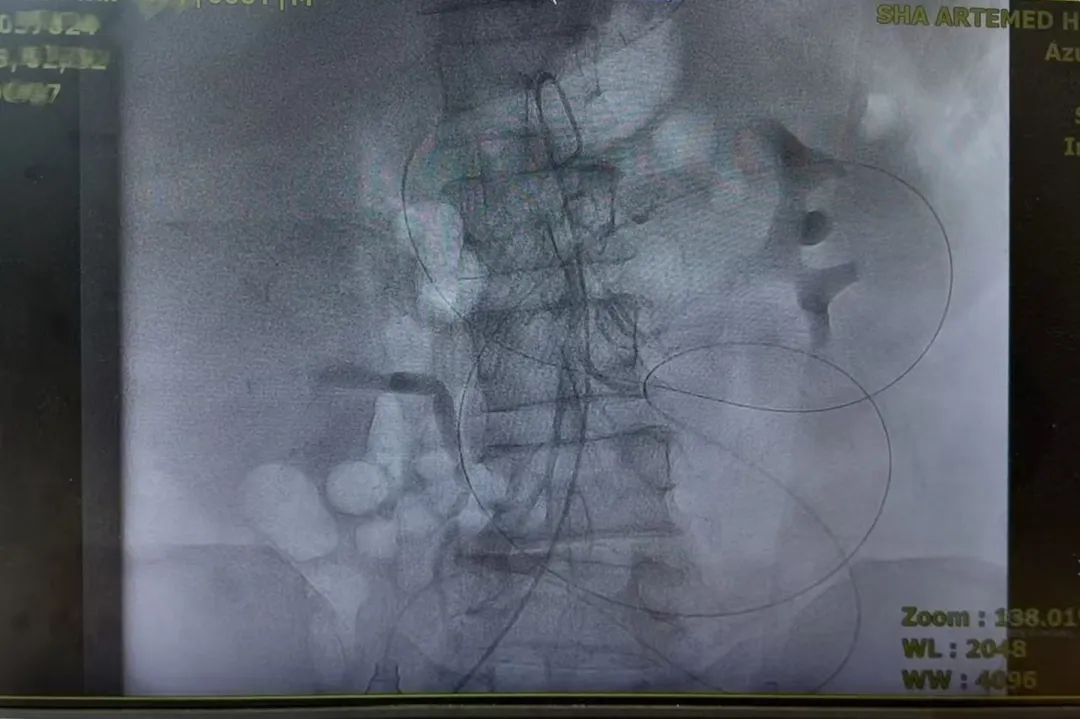

术中影像资料

住院后,医生针对患者肿瘤负荷大、合并小肠梗阻的情况,给患者经动脉灌注化疗。2026年1月14日,接受腹腔干动脉、肠系膜上下动脉造影置管,局部灌注奥沙利铂和氟尿嘧啶等药物,目的是直接作用于肿瘤、缓解梗阻。